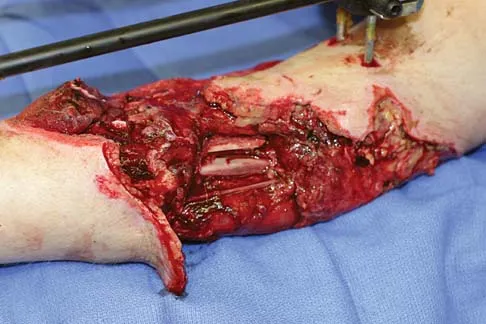

Question 70

A healthy 25-year-old man sustains a grade IIIB open tibial fracture. Following appropriate debridement, irrigation, and stabilization with an external fixator, the soft-tissue injury is shown in Figure 30. What is the most appropriate definitive soft-tissue coverage procedure?

Explanation